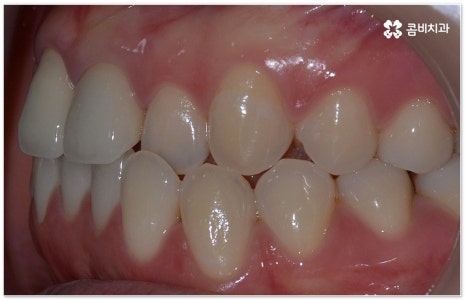

요즘 가장 많이 쓰이는 치아교정장치 인 클리피씨는 치아 색상의 세라믹 브라켓을 이용하기 때문에 심미성도 뛰어나고 자가결찰방식을 이용하여 보다 적은 힘으로 지속적이고 부드러운 치아 이동을 할 수 있도록 고안된 장치이므로 통증을 줄여줄 뿐 아니라 보통 2년 남짓 걸렸던 전체 교정 기간 역시 6개월 정도 감소시켜 줄 수 있습니다. 환자분들의 상황에 따라 내원 횟수 역시 줄일 수 있기 때문에 업무가 많이 바쁜 직장인분들의 경우에도 이용할 수 있다는 장점을 가지고 있어요.

부정교합을 개선할 때 교합이 어긋난 정도가 심하고 구조적인 원인이 커서 부분 교정이 아닌 전체 교정이 필요한 케이스인 경우라고 해도 말씀드렸던 클리피씨 교정 장치 또는 보다 심미성을 강조한 치아교정장치 들의 도움을 통해 다른 사람과 얘기를 하거나 음식을 먹을 때 브라켓이 두드러지게 드러나는 부담을 줄일 수 있으니 설측교정, 콤비교정, 투명교정, 인비절라인 등에 대해서 한 번 알아보시고 각자에게 맞는 방법으로 교정 치료를 시작해 보시길 권유드리고 있어요.